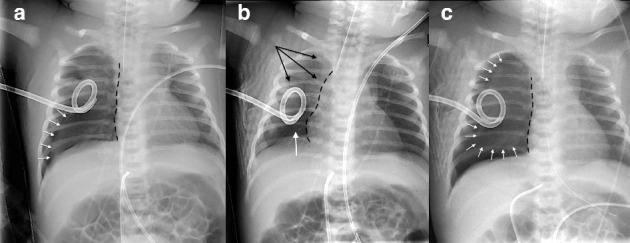

Cardiac tamponade is a challenging clinical situation in preterm newborns. We report the first case of an iatrogenic cardiac tamponade secondary to direct myocardial disruption with pericardial penetration following unsuccessful attempts to drain a right tension pneumothorax in a 34-week premature female newborn. The pathophysiologic mechanisms involved are discussed.

心脏压塞在早产新生儿中是一种具有挑战性的临床情况。我们报告了首例医源性心脏压塞病例,该病例发生在一名34周早产女婴身上,在尝试引流右侧张力性气胸失败后,因直接心肌破裂伴心包穿透继发心脏压塞。文中讨论了所涉及的病理生理机制。